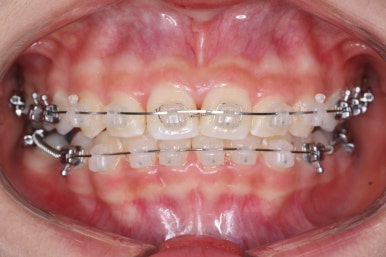

치료 종료 후의 모습입니다.

치아들이 가지런하게 되었고, 나오지 못하던 치아도 잘 나와서 가지런해졌습니다.

해당 부위 앞뒤로 쓰러져 있던 치아들도 축이 바로 잡혔고, 자연스레 위-아래 치아의 중앙선도 맞아졌습니다.

부산치아교정잘하는곳 키다리아저씨치과에서 이번 청소년 환자분께 치료하느라 소요된 기간은 총 16개월이였습니다.